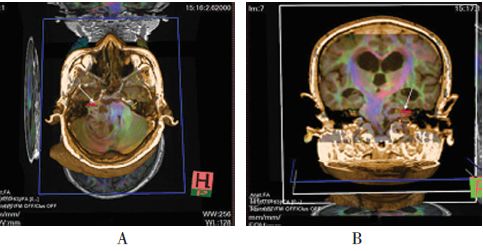

患者听神经瘤面神经可DTI成像技能显现,面神经均坐落肿瘤腹侧(见图1)。7例坐落肿瘤中部1/3,2例坐落肿瘤下部1/3,2例坐落肿瘤上部1/3,术前定位成果与术中所见符合率为100%。

图1 面神经DTI图画。A:横断位;B:冠状位。白色箭头示面神经方位